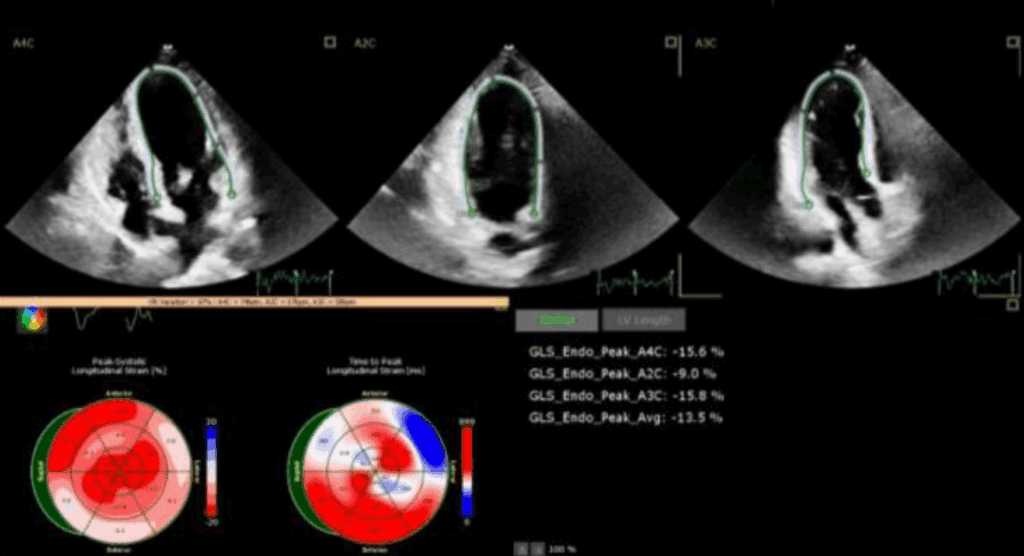

Odkształcenie mięśnia sercowego (strain) jest metodą diagnostyczną oraz coraz lepiej udokumentowanym parametrem prognostycznym, który uzupełnia standardowe przezklatkowe badanie echokardiograficzne (ang. transthoracic echocardiography – TTE).